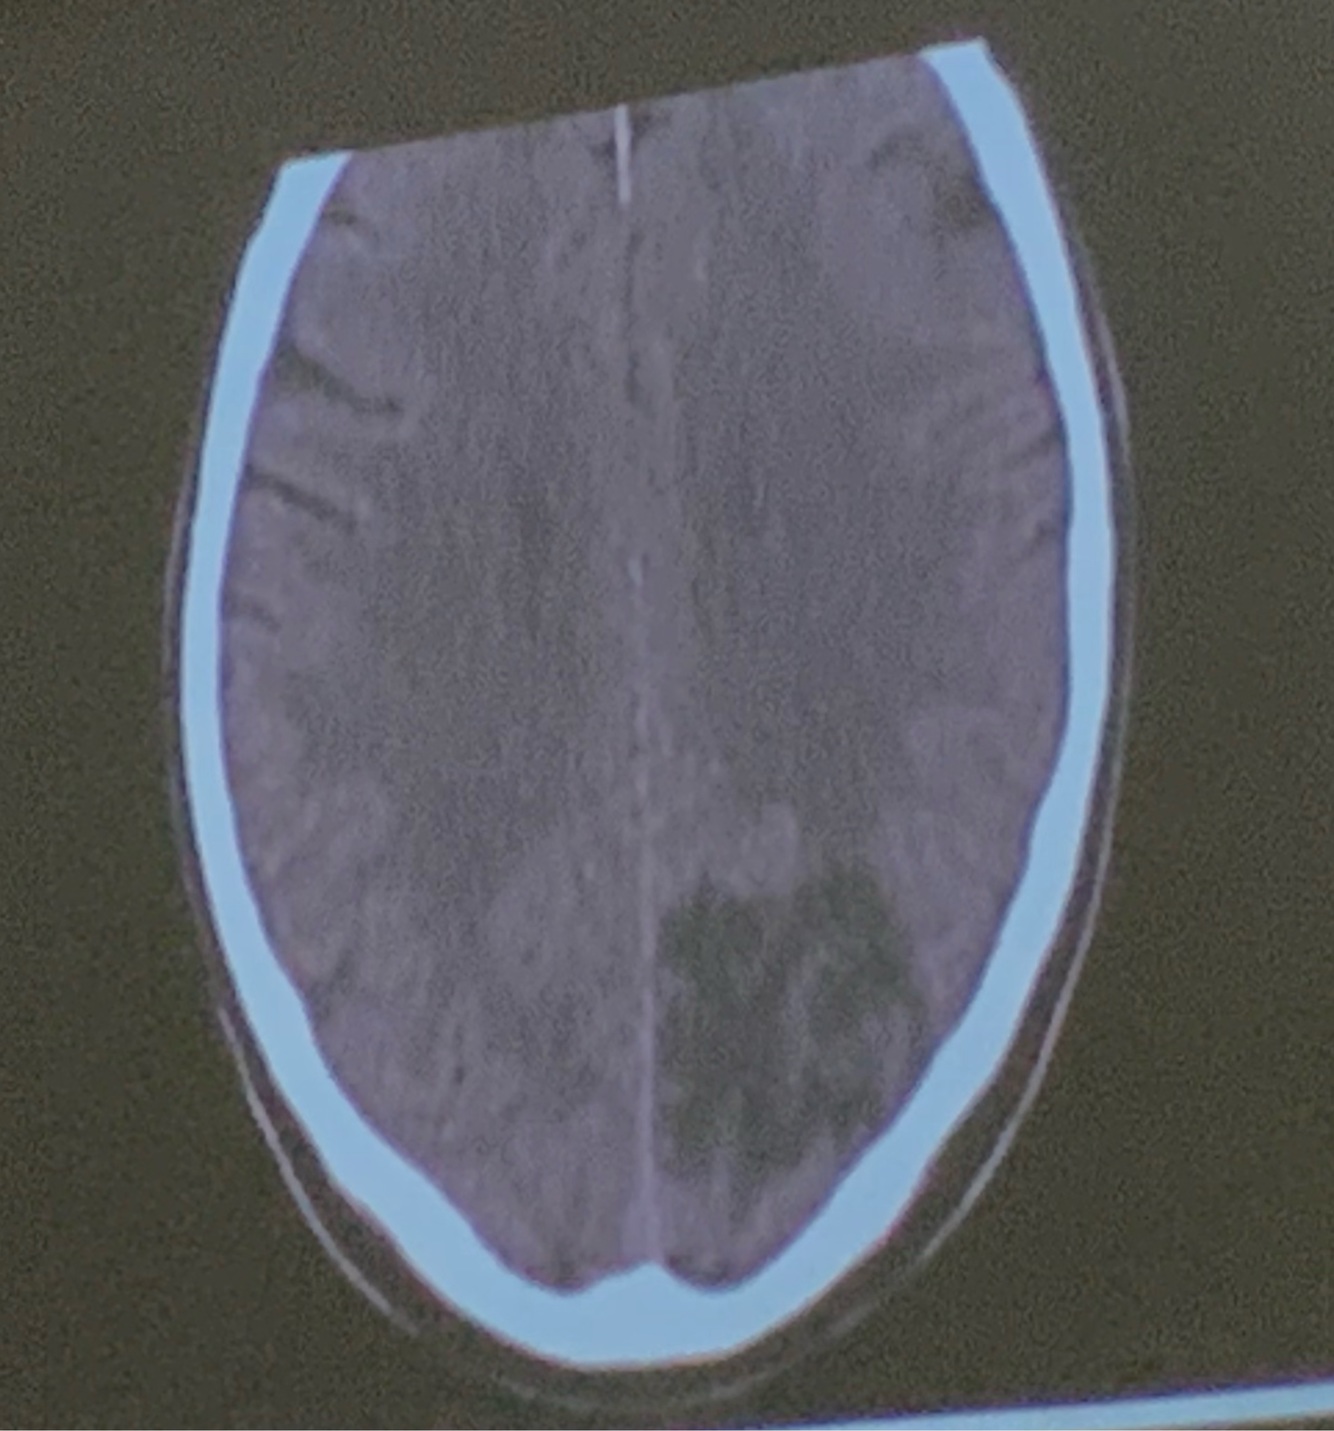

11

Que arteria se encuentra afectada

ACA